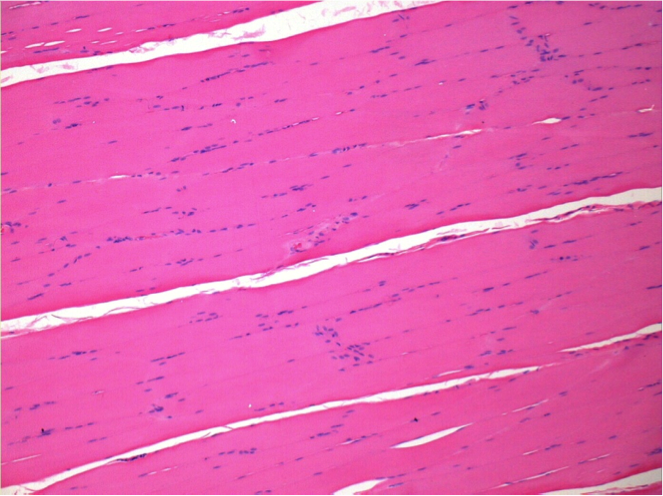

L:Pretibial-No treatment